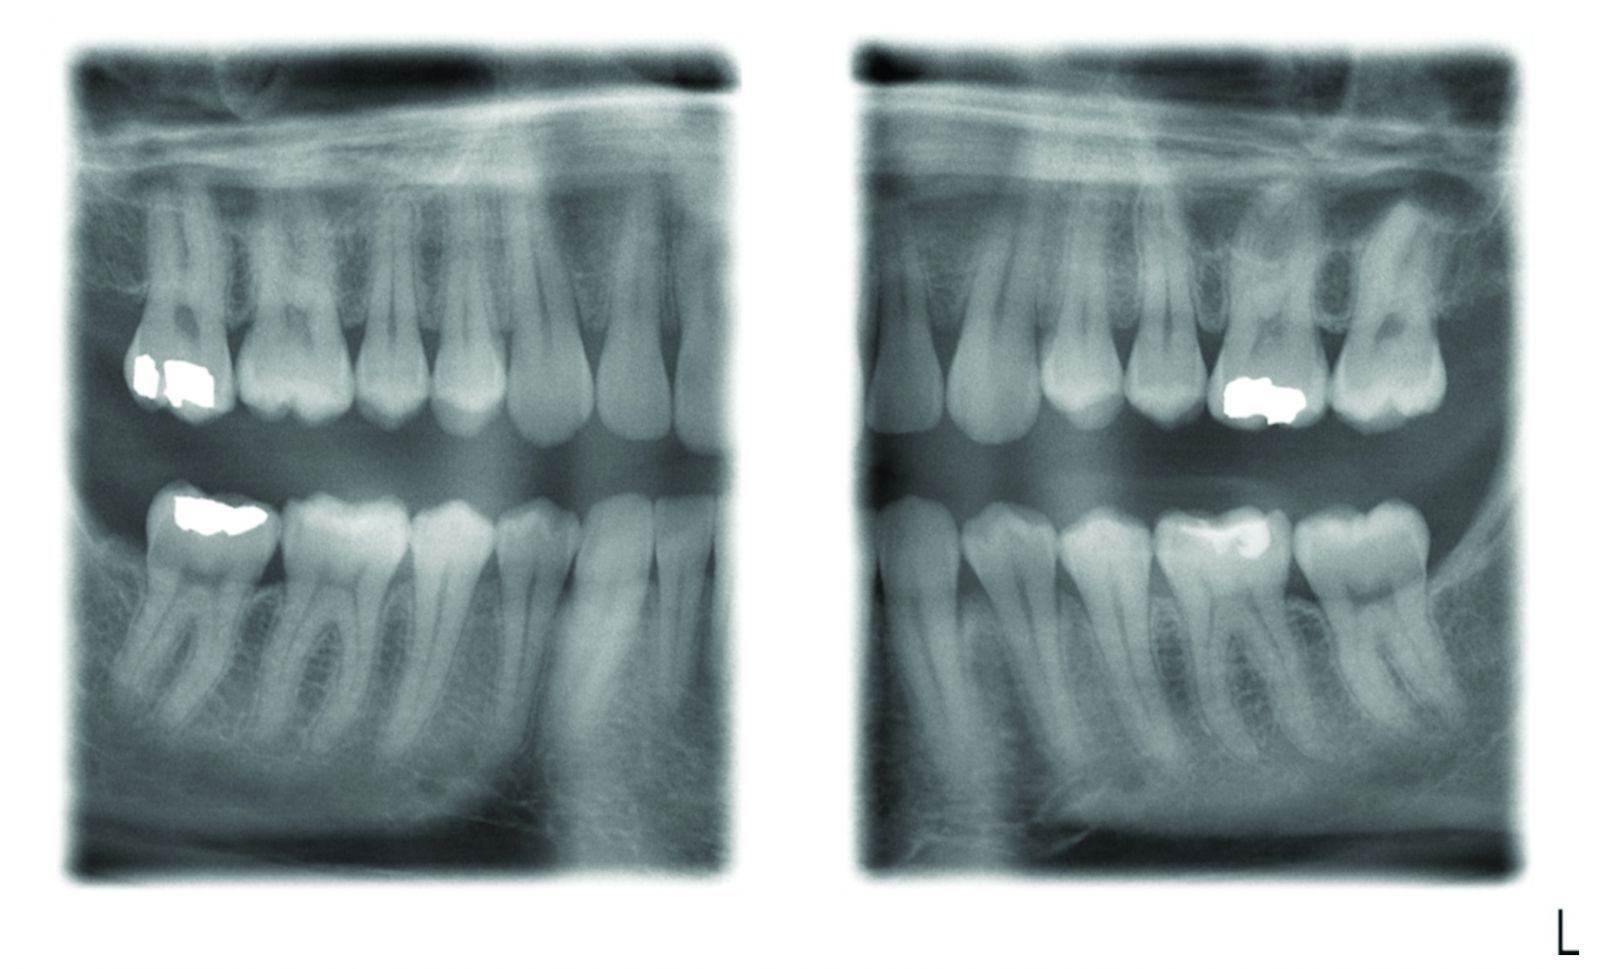

According to Dr. John Flucke, DPR Technology Editor, the process of digital radiography is simple, reliable and provides images that are nothing short of amazing. At this point in time if you’re still using film, the long shadow of Father Time is gaining on you… faster than you can probably imagine. To put it succinctly, digital radiography is no longer a matter of “if,” it’s a matter of “when."

According to Dr. John Flucke, DPR Technology Editor, the process of digital radiography is simple, reliable and provides images that are nothing short of amazing. At this point in time if you’re still using film, the long shadow of Father Time is gaining on you… faster than you can probably imagine.

To put it succinctly, digital radiography is no longer a matter of “if,” it’s a matter of “when."